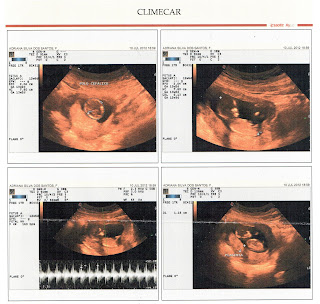

você a final a Utrassonografia

Morfológica do Priemiro Trimestre c/ Translucencia Nucal, é onde o médico mede cada órgão, cada osso,

cada parte do corpinho do bebê, a partir daí podemos saber se ele está se

desenvolvendo adequadamente e translucencia nucal( é um líquido que os bebês

apreresentam na nuca enquanto eles estão entre as semanas 11 e 13) e também

mede esse liquido e através dele é possível saber se o bebê apresenta alguma

síndrome (como a síndrome de Down, por exemplo).

vestígios se você era menino ou menina! O relatório que o medico nos deu

concluiu que você está com morfologia preservada com 12 semanas e 06 dias,com

crescimento fetal adequado e translucência nucal normal. Ufaaaaaaa!!!! Veja algumas

imagens.